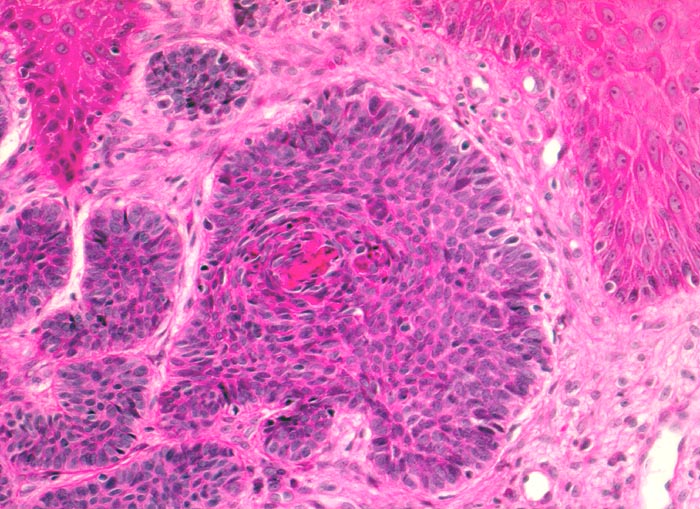

Morphologische Merkmale:

• Fokale oberflächliche Ulzeration bzw. Erosion der Epidermis über dem Tumor.

• Solide blaue Tumorzellplatten in der Dermis, teils mit Kontakt zur Epidermis.

• Die zytoplasmaarmen Tumorzellen ähneln Basalzellen der Epidermis.

• Palisadenförmige Anordnung der Tumorzellen am Rand der Zellplatten.

• Retraktionsartefakt zwischen Tumor und Stroma.

• Tumorstroma bestehend aus Fibroblasten, lockeren Kollagenfasern, hellblauen Muzineinlagerungen und chronischem Entzündungsinfiltrat.

• Im Zentrum einzelner Tumorzellplatten Verhornung, Tumornekrosen oder Hohlraumbildungen.

• Die Dermis in der tumorfreien Haut zeigt eine deutliche solare Elastose als Zeichen der chronischen UV Schädigung.